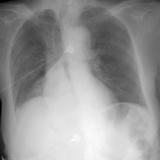

Mass RLL collapse 5 PA

Date: 03/02/2006

Views: 4092